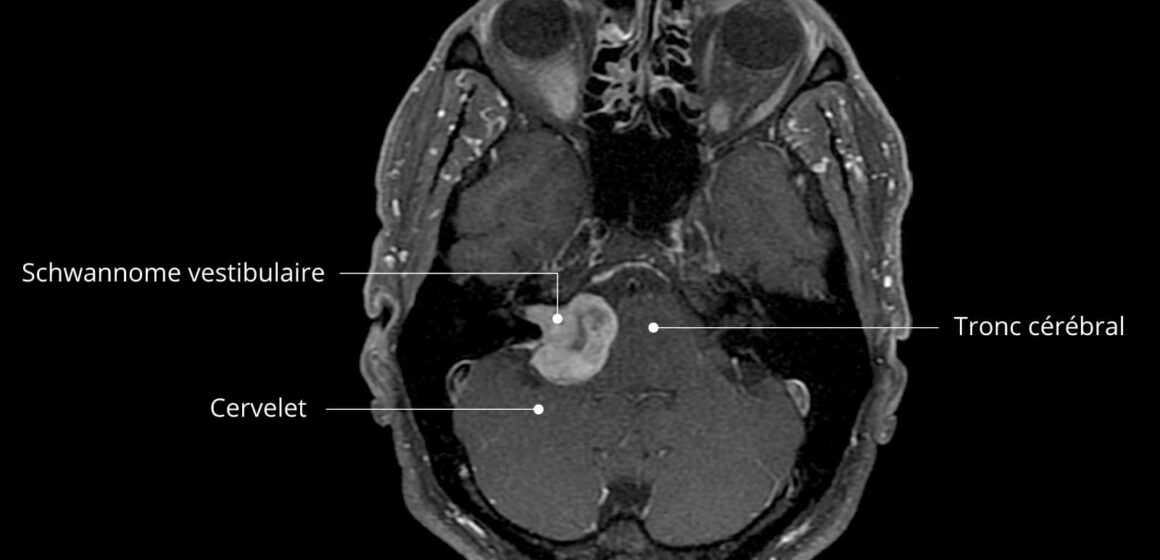

Objectif : Les personnes atteintes d’un schwannome vestibulaire souffrent de vertiges, de troubles de l’équilibre et d’une diminution des fonctions, ce qui entraîne une baisse de leur qualité de vie.